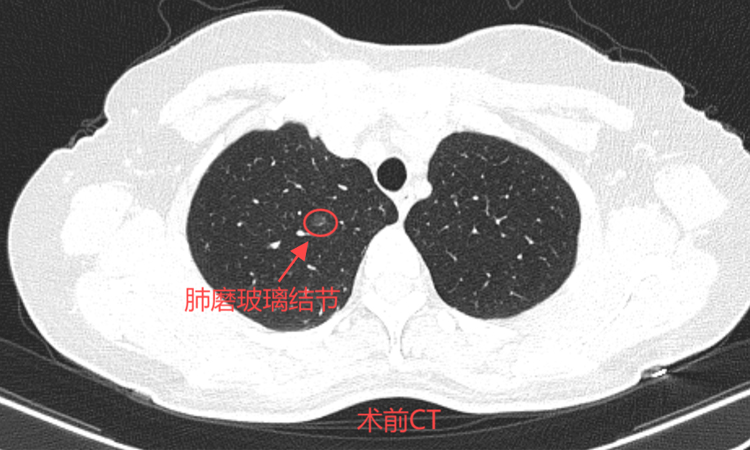

46岁的孙女士一年前在一次偶然的体检中发现自己双肺有多发磨玻璃结节。在医生的建议下,决定先进行随访,等结节有变化了再做处理。今年复查时发现最大结节已经达0.9*0.8cm,因担心癌变可能,于近日前往北京某三甲医院就诊,看诊后专家建议行消融治疗,经过多方咨询后就诊于我院。

患者术前肺多发磨玻璃结节